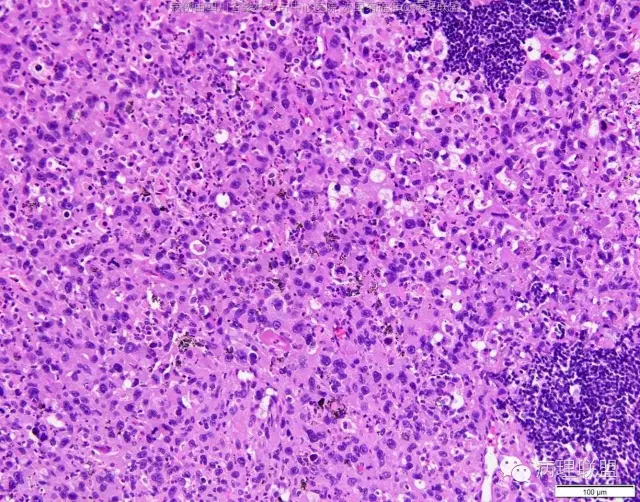

M/47 肺部占位( 肺大细胞癌?)

M/47 肺部占位,大小2*1*0.6cm(病例由四川攀枝花市中心医院 沈国菊提供,致谢!)

@张丽 免疫组化腺癌,鳞癌,神经内分泌,恶黑标记均为阴性,只有广谱CK跟Vimentin阳性,准备发大细胞癌

@沈国菊 肺大细胞癌的签发有时是个排他性诊断,我的体会:大细胞的标准:按淋巴细胞直径3倍来算,需要大于这个值,不能等于(从图给出,符合)。神经内分泌的标记(CD56 SYN CgA)完全阴性的可能性不是没有,建议重做试试;细胞的异型性大(符合);Ki67的指数高,应该非常高(您这里没有给出)。这仅仅是我个人体会,我说的不一定正确。

感谢您的精彩病例,采图非常漂亮,并且有标尺(特别赞)。魏老师,Ki-67阳性大于90%,送检7组淋巴结6/7见肿瘤转移。